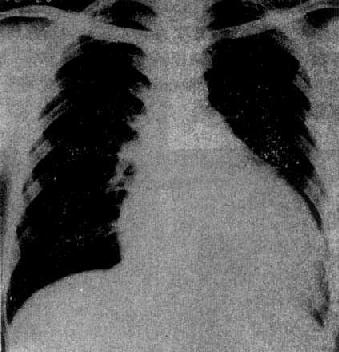

图3-2-16 二尖瓣关闭不全并狭窄

心增大呈二尖瓣型,右心室增大,肺动脉

段突出,左心耳增大,有肺瘀血

图3-2-17 慢性肺原性心脏病

心呈二尖瓣型,右心室增大,肺动脉突出,但无左心耳增大。肺动脉扩张,尤以右下肺动脉为明显,有肺门截断现象,说明有肺动脉高压。肺纹理增强,肺透明度增加,膈平而低,说明有慢性支气管炎和肺气肿